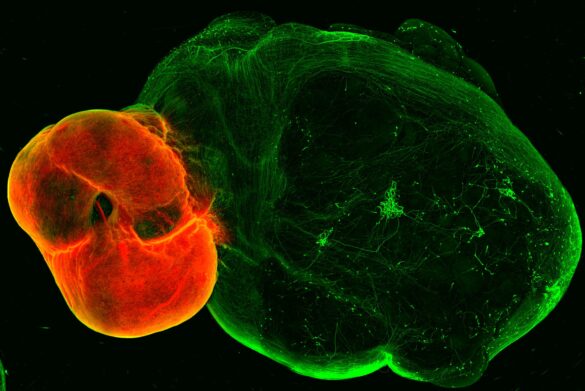

Neurones dopaminergiques dans le mésencéphale ventral (rouge) et projections ventrales du mésencéphale dans les tissus striatal et cortical (vert). Crédit : (c) Daniel Reumann/IMBA

L’équipe a d’abord développé des modèles organoïdes du mésencéphale ventral, du striatum et du cortex – les régions reliées par les neurones dans le système dopaminergique – puis a développé une méthode pour fusionner ces organoïdes. Comme c'est le cas dans le cerveau humain, les neurones dopaminergiques de l'organoïde du mésencéphale envoient des projections vers les organoïdes du striatum et du cortex.